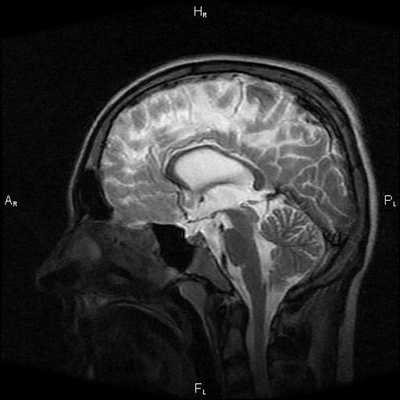

Магнитно-резонансная томография

МРТ позволяет легко установить диагноз. При отсутствии изображений с насыщением жировой ткани в качестве полезного подспорья можно использовать артефакт химического сдвига. Сигнальные характеристики соответствуют жировой ткани:

- T1: высокая интенсивность МР сигнала

- T2: высокая интенсивность МР сигнала

Магнитно-резонансная томография. Этот способ визуализации подходит для уточнения типа опухоли, поскольку на снимках хорошо различимы разные типы мягких тканей.

Компьютерная томография. Результаты КТ дают возможность отличить жировик от других опухолей и опухолевидных структур.

При МРТ головного мозга установлено: МРТ признаки хронической недостаточности мозгового кровообращения; выраженная открытая внутренняя гидроцефалия, свидетельствующая о признаках атрофических изменений в головном мозге.